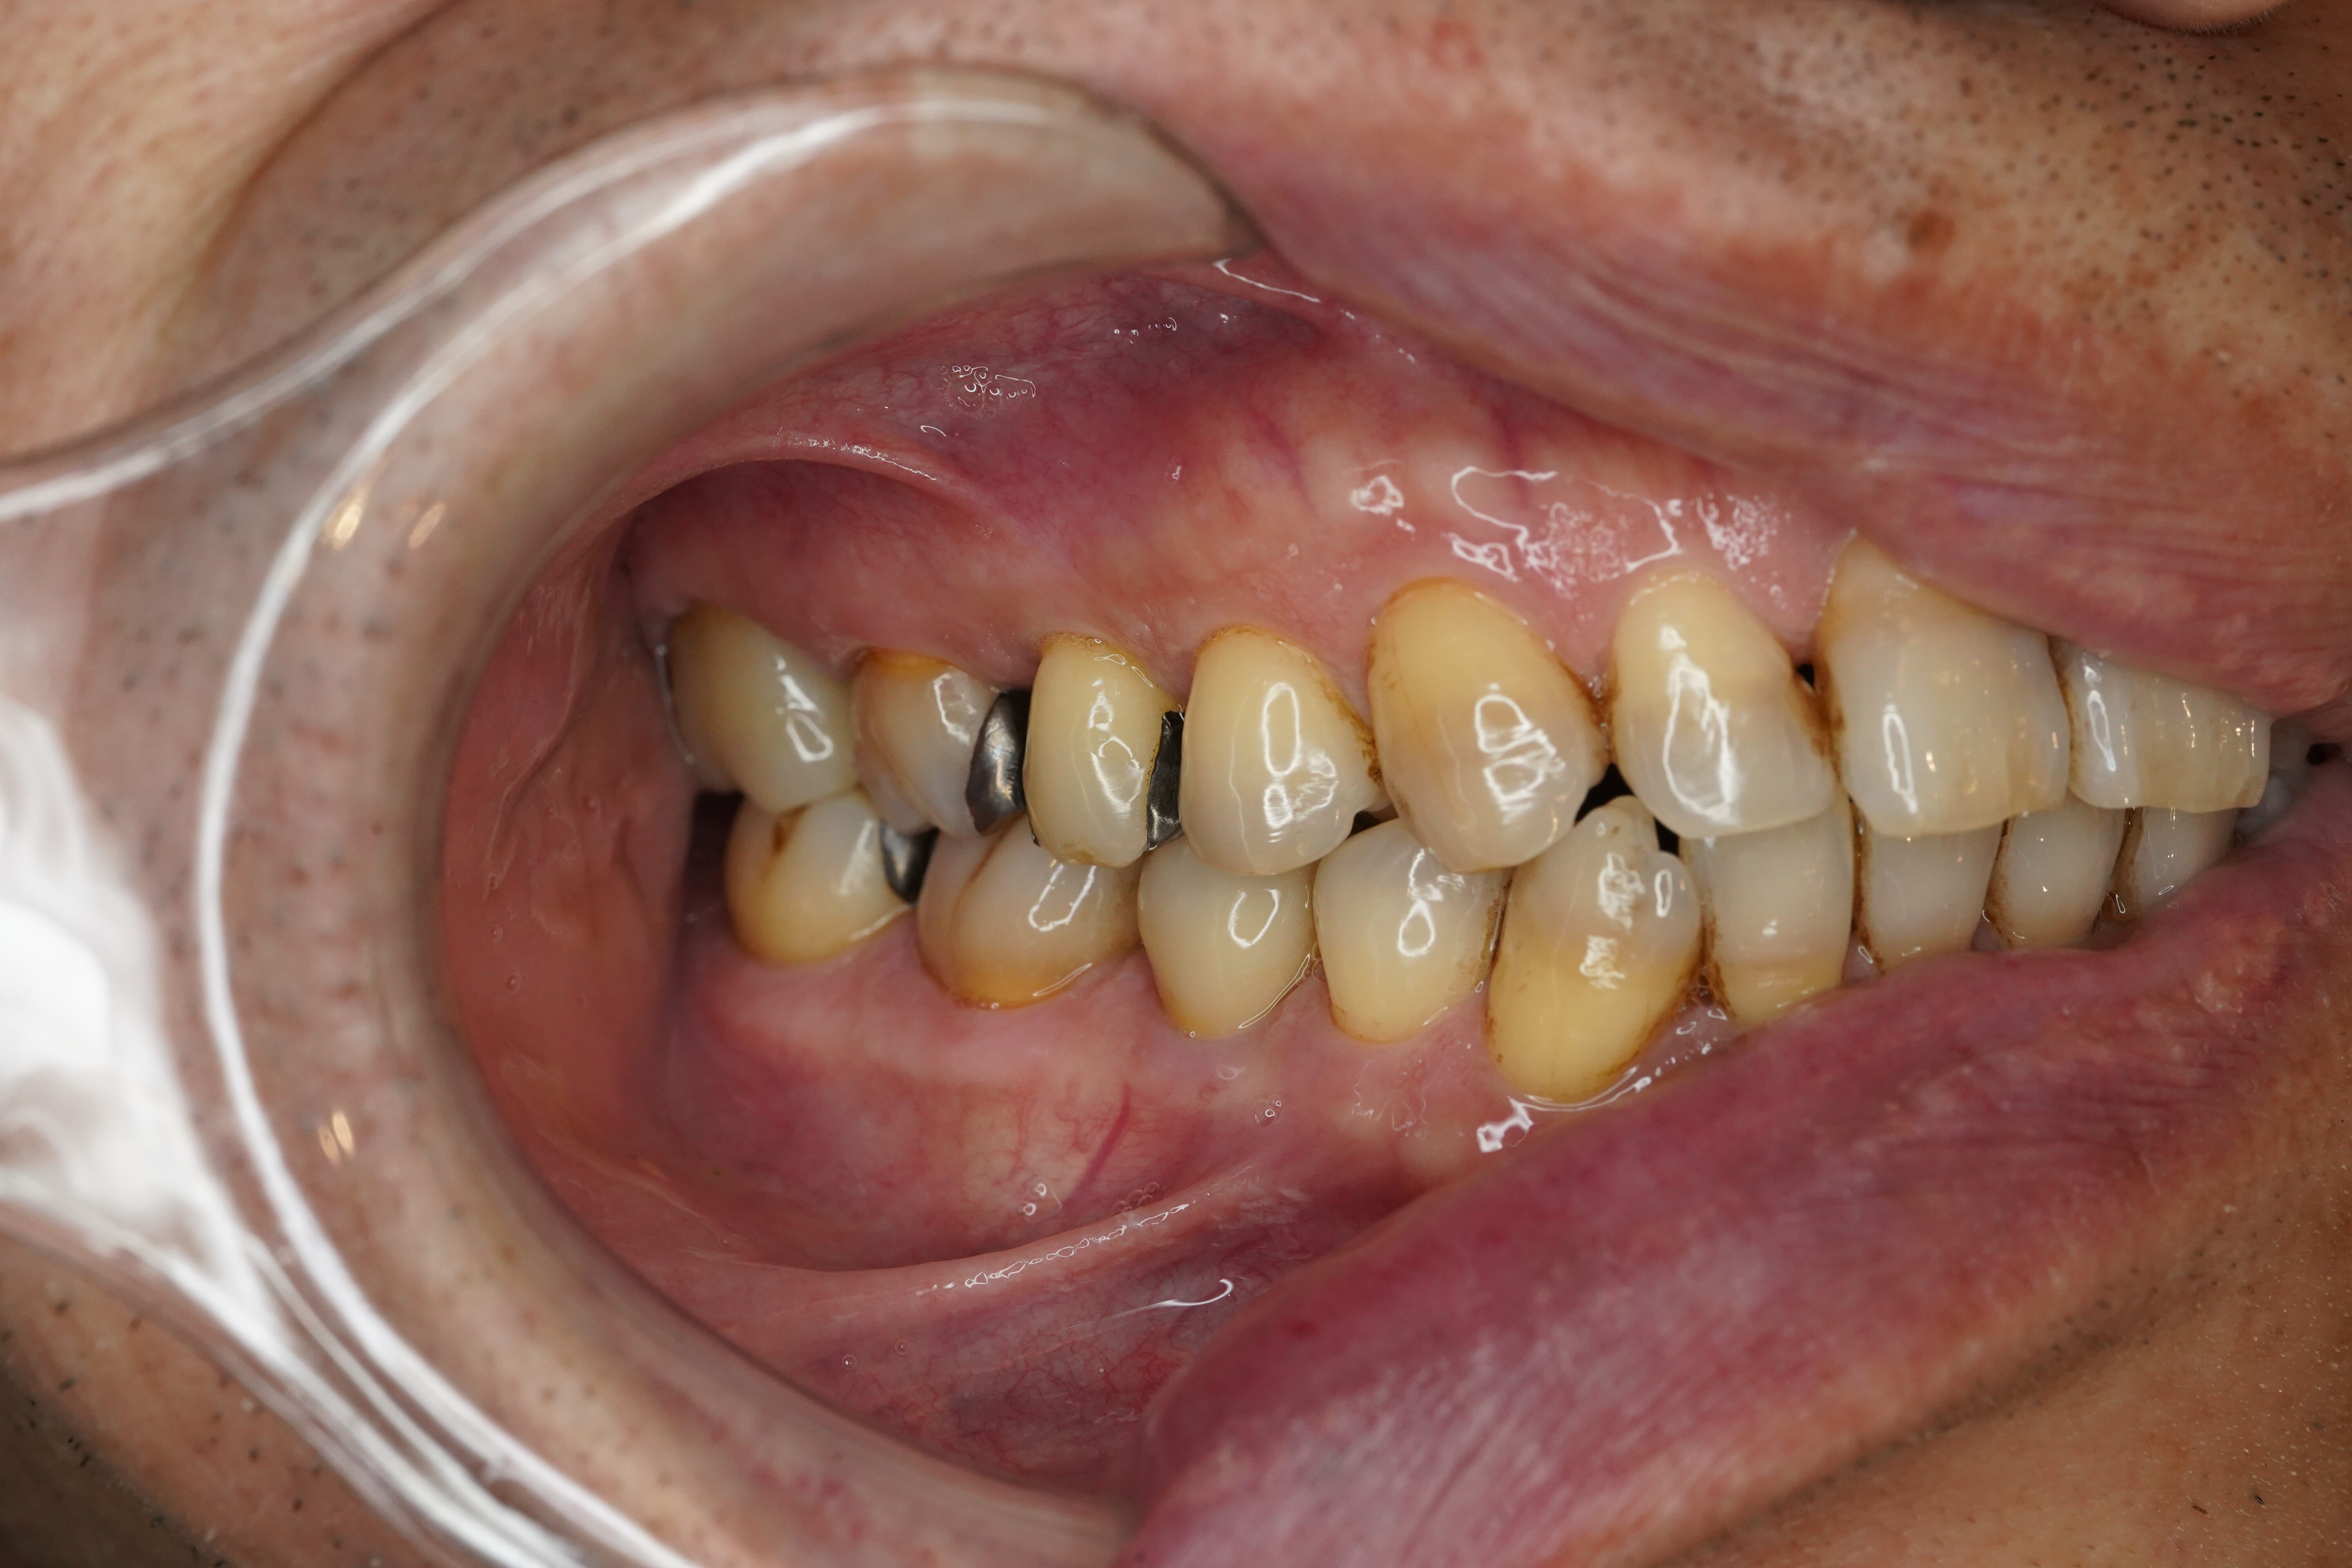

右上3本をMTAとフルジルコニア

今回は右上第一・二小臼歯と第一大臼歯の3本をまとめてMTA &フルジルコニアで治療したケースのご紹介です💡

もともと右上第二大臼歯を感染根管治療・ファイバーコア・フルジルコニアで治療をされていました

その時に手前の歯に虫歯が見つかりその歯にはメタルの詰め物が入っていました

どの歯も同じ時期にメタルの詰め物をされたそうでまとめての治療を希望され今回処置をすることとなりました

🦷治療内容:MTAとフルジルコニア

🦷担当医:Dr.小林

🦷技工所:プロミネント